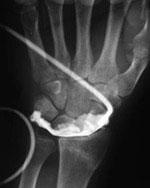

при това изследване в ставата се инжектира рентгенконтрастна материя, на чийто фон вътреставните структури стават видими на обикновена рентгенография; артрографията има все по-малко приложение, поради изместването и от магнитния резонанс;